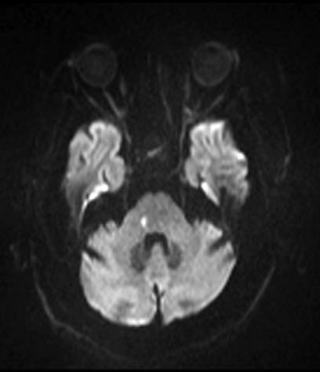

MRI DWI

後頭葉、側頭葉に古い脳梗塞があります。脳幹部にDWIで高信号を示す病変が認められました。この部位は橋排尿中枢(PMC)と言われている部分です。よって、脳幹梗塞による神経因性膀胱と診断されました。橋排尿中枢が障害されていれば排尿ができなくて当然と考えたくなりますが、では排尿が出来ないのは、DUだけで説明できるのでしょうか。尿道括約筋の弛緩が出来ないのかもしれませんし、すでに脳幹梗塞の影響は消失し尿閉による膀胱過拡張のためのDUだけが残っているのかもしれません。実際のところはよく分からないと思います。